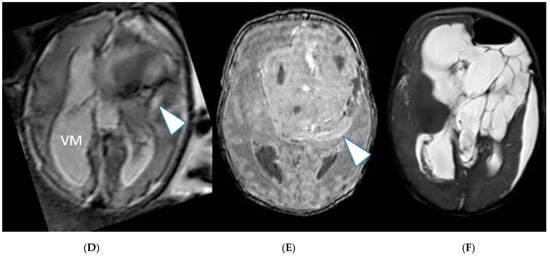

2. Case Series